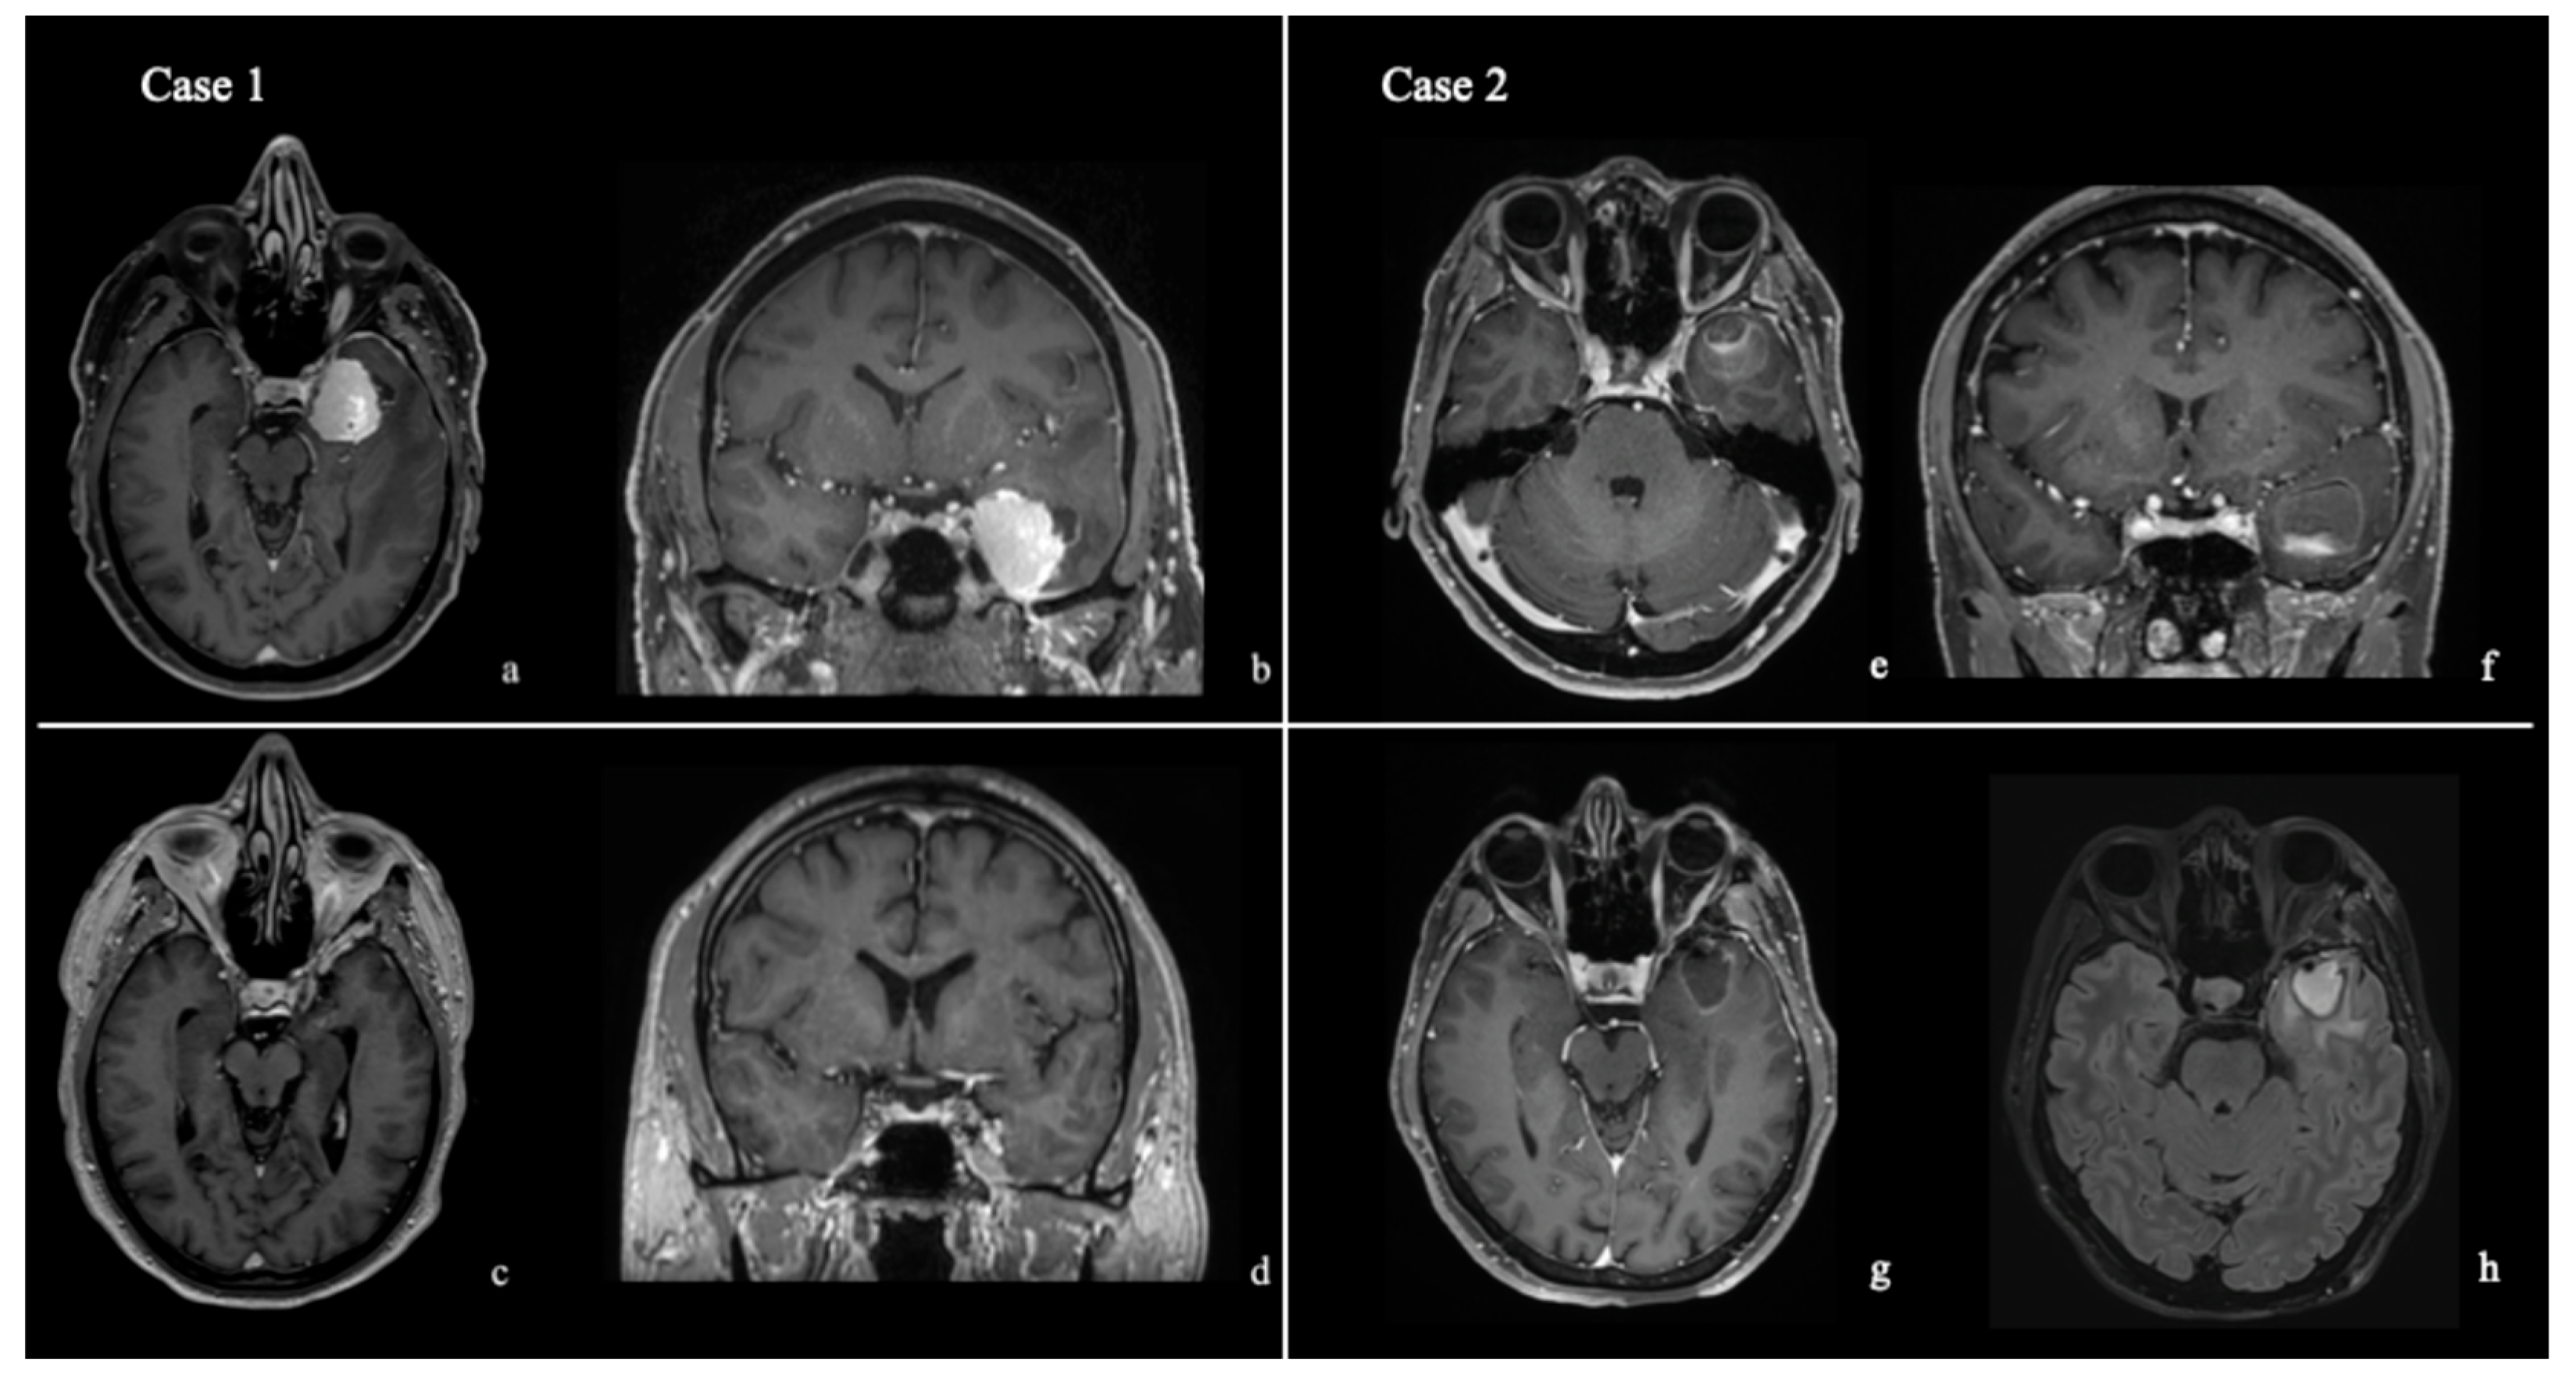

2.3. Bony Phase

2.4. Extradural and Intradural Phases